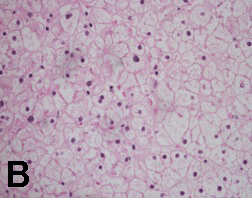

Case 2: A 14-year-old Hispanic male was admitted for evaluation of lower leg edema and massive hepatomegaly. He was diagnosed with T1DM at three years of age. His glycemia had been poorly controlled resulting in several episodes of DKA. Physical exam demonstrated an enlarged liver palpable to the umbilicus. His weight was between 25th and 50th percentiles and his height was below 5th percentile. He was in Tanner 1 for pubic hair and Tanner 3 for testicles. His HbA1c ranged from 9 to 12%. His liver tests showed AST - 878 U/L, ALT - 751 U/L. The liver ultrasound showed markedly enlarged liver measuring 26 cm in span. After evaluation for chronic liver disease was negative, a liver biopsy was performed. The pathology reported glycogen-rich cytoplasm and glycogenated nuclei of hepatocytes with no steatosis, inflammation or fibrosis (Figures 1 and 2). He underwent strict diabetic control, his liver enzymes returned to normal within 4 weeks (AST - 24 U/L, ALT 26 - U/L, HbA1c - 8.2%). Unfortunately, due to multiple social circumstances, he could not maintain good glycemic control. He continues to have hepatomegaly, a high HbA1c of 12% and mild transaminase elevation.

Figure 1: Hematoxylin and eosin stain of needle liver biopsy showed hepatocytes diffusely swollen and enlarged, with rarified cytoplasm and centrally placed nuclei. The cells were arrayed in a mosaic pattern throughout the lobules.

Figure 2-A: Periodic Acid-Schiff stain showed A) strong cytoplasm positivity, which B) disappeared upon pre-treatment with diastase (PASD stain), consistent with glycogen accumulation.

Figure 2-B: Periodic Acid-Schiff stain showed A) strong cytoplasm positivity, which B) disappeared upon pre-treatment with diastase (PASD stain), consistent with glycogen accumulation.

Liver biopsy is helpful to confirm the diagnosis of GH. Histologic features in GH are characterized by large, swollen, glycogen-laden hepatocytes and glycogenated nuclei without significant fatty change, inflammation, lobular spotty necrosis or fibrosis. [2] This was evident in our three biopsy cases. Steatohepatitis is defined as the combination of steatosis, lobular inflammation, acidophilic bodies, and pericellular fibrosis. The differential diagnosis of GH includes NASH and glycogen storage diseases. However, the diagnosis of T1DM-associated GH can be considered based on a history of poorly controlled T1DM and response to euglycemic control. Other features of Mauriac syndrome, though not necessary, can, if present, assist with the diagnosis.